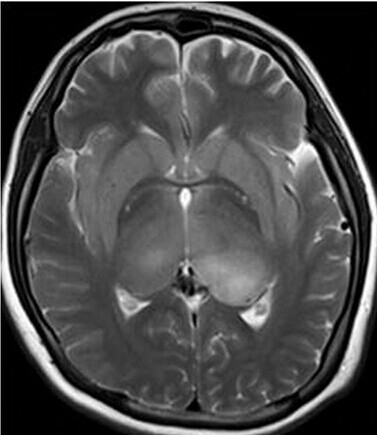

患者:女,23岁,主因嗜睡、言语不利三个月,四肢无力、吞咽障碍3个月入院。

【正确答案】D 大脑胶质瘤病

大脑胶质瘤病的特征性影像学表现是:

(1)肿瘤常累及2-3个脑叶,白质改变为主,占位效应不明显或轻度占位效应;

(2)病变区大脑结构相对保留;

(3)增强后多无强化。